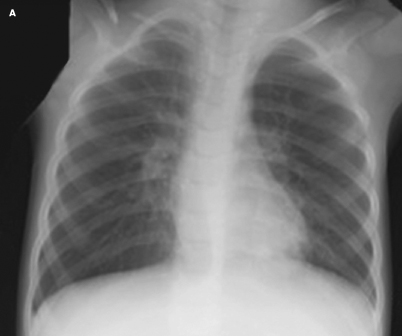

community-acquired pneumonia

Linda S. Nield, MD

<P>This brief update summarizes the highlights of the recently published clinical practice guidelines on the management of community-acquired pneumonia to aid the practicing clinician in managing this...